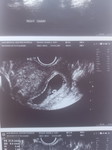

12weeks Preggy

12weeks and 5days po ako pregnant. Normal lang po ba na mas gusto mo matulog at hindi ka mabilis magutom or hindi ka matakaw? At pag 12weeks po ba nararamdaman na po ba ang movement ni baby or hindi pa po? Thank you